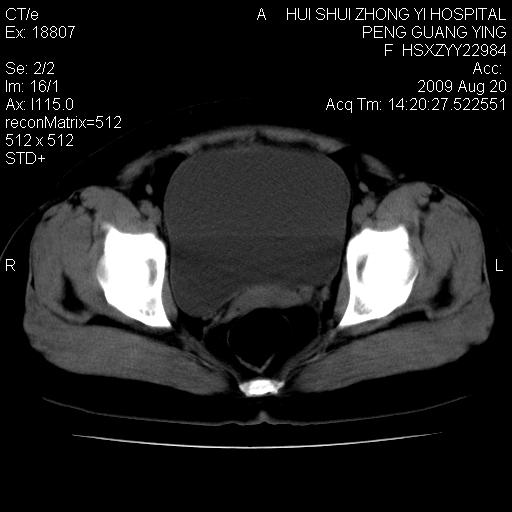

标题: CT21707:女,42岁,因发现下腹部包块2月。 [打印本页]

标题: CT21707:女,42岁,因发现下腹部包块2月。

病灶来源——子宫?附件?

从平扫角度看本人还是倾向于子宫肌瘤诊断,宫腔少量积液。

目前的影像表现显示肿块位于腹腔及盆腔,但具体定位,分清来源较困难,是否来源于卵巢、子宫无法定论,子宫直肠及子宫膀胱周围脂肪间隙尚较清晰,如果患者有过腹腔好或者盆腔手术史,也可以形成不典型的血中,最好手术后定为定性,我期待结果。

软组织密度,与子宫一致。双侧卵巢形态、密度好,不支持来源于卵巢。